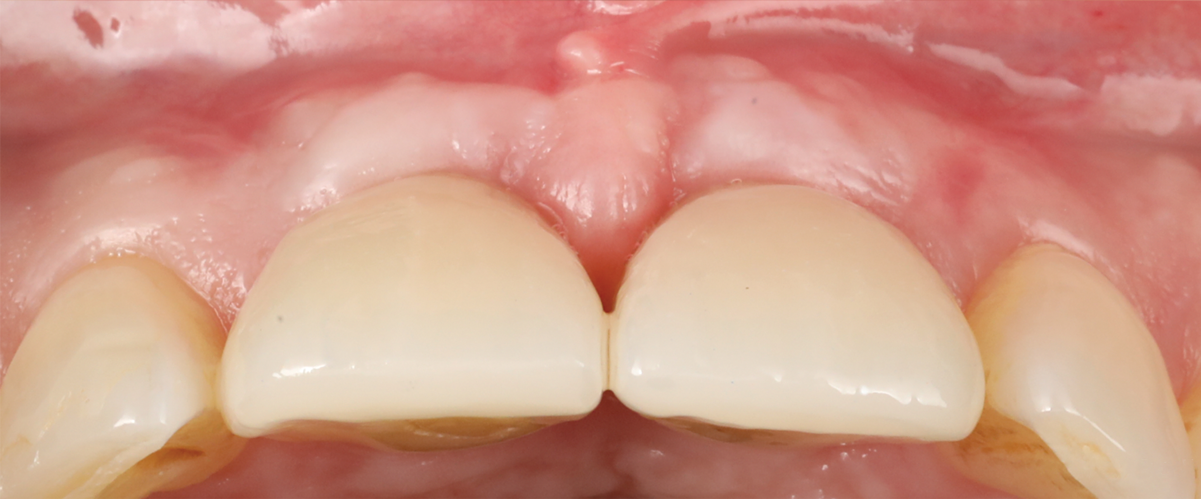

Fig 14. Final outcome at 1 year.

Figure 14

Figure 14 depicts the final outcome at 1 year (which can be compared to the pretreatment photograph in Figure 1). Figure 15 through Figure 18 show clinical comparisons of the outcome at baseline and 1 year, while Figure 19 and Figure 20 provide an ultrasonographic characterization of the soft tissue at baseline and 1 year. The facial probing depths at 1 year were 3-3-3 mm for implant No. 8 and 3-2-3 mm for implant No. 9. The patient was highly satisfied with the esthetic outcomes and overall treatment.

Fig 15. Clinical comparison of the volumetric gain obtained with the intervention, frontal views. Fig 15: Frontal view at baseline. Fig 16: Frontal view at 1-year post-treatment.

Figure 15

Fig 16. Clinical comparison of the volumetric gain obtained with the intervention, frontal views. Fig 15: Frontal view at baseline. Fig 16: Frontal view at 1-year post-treatment.

Figure 16